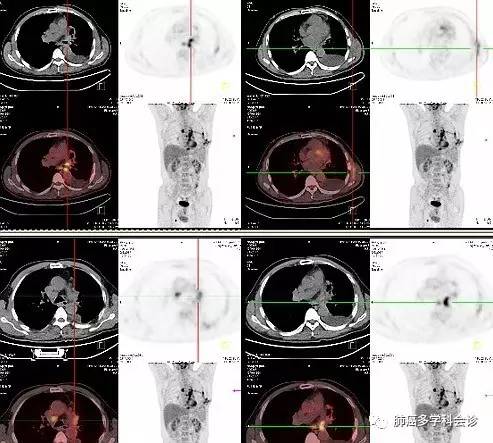

术后1月余PET-CT示:

• 左肺粘液表皮癌术后改变,左肺门不规则软组织密度影代谢活跃,考虑肿瘤残留或复发。左侧胸腔积液;

• 纵隔主动脉弓旁、右下气管旁、主肺动脉窗及隆突下肿大淋巴结代谢活跃,考虑转移;

• L3椎体左侧横突局部代谢活跃,疑转移。

• 腹膜后多个小淋巴结影部分代谢较活跃4.右侧大腿大收肌代谢活跃灶。